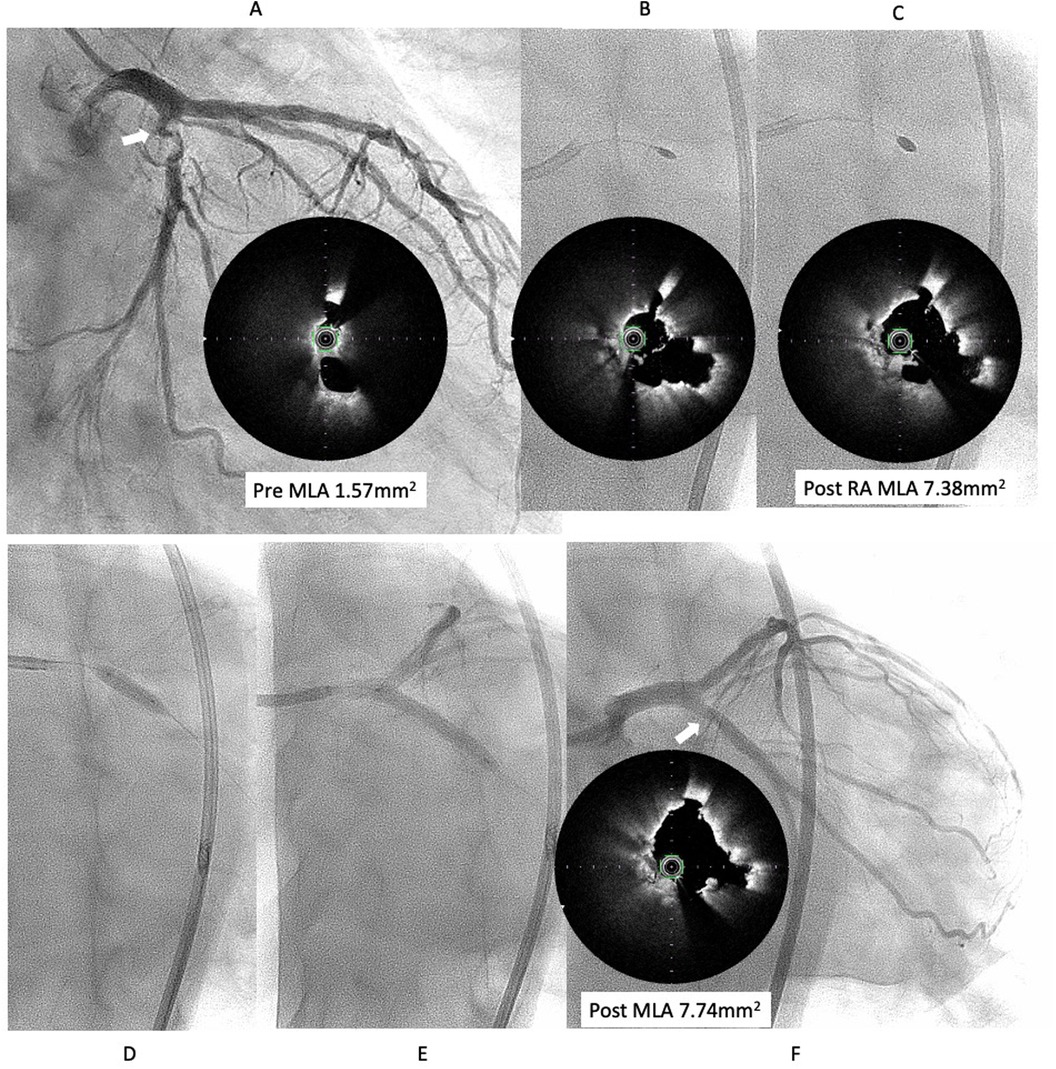

However, six months later, the symptoms recurred, and CAG revealed restenosis at the LCX (Figure 2A). Therefore, we proceeded with repeat PCI. The lesion appeared hazy on angiography, with small channels visible within the lesion. We selected an 8-French system, considering the possible need for a large-diameter Rotablator. IVUS showed that the lumen was filled with proliferative calcified tissue. While IVUS indicated features suggestive of a CN, it had already been treated six months earlier, so the proliferative CN tissue was assumed to be not very hard. Therefore, we attempted to remove the CN using directional coronary atherectomy (DCA). We selected a medium-size ATHEROCUT catheter (NIPRO, Japan) and performed a total of 31 cuts at a maximum pressure of 40 psi. After removing a total of 12.2 mg of CN tissue with DCA, the lumen was significantly enlarged (Figure 2B). Next, the lesion was dilated using a CB 3.25 mm, which was a quarter size larger than the previous one, followed by a SeQuent Please 3.5 × 20 mm (Figures 2C,D). The final angiogram showed a no residual stenosis without any complications (Figure 2E). However, 6 months later, the symptoms recurred, and CAG showed restenosis again with irregular channel (Figure 3A). Despite recurrent restenosis of the lesion, we decided to perform repeat PCI for this lesion because the patient was at high risk for bypass surgery due to hemodialysis. This time, we also chose an 8Fr system. We needed to take a different approach from the previous two procedures. OFDI revealed a very eccentric lumen with an irregular surface. Both eruptive and non-eruptive CNs were present in the same lesion.

Coronary angiography images show pre- and post-intervention analysis of a coronary artery. Panel A shows pre-intervention with a minimal lumen area (MLA) of 1.57 square millimeters. Panels B and C display intra-vascular ultrasound images with a post-rotational atherectomy (RA) MLA of 7.38 square millimeters. Panels D and E depict catheter positioning. Panel F highlights post-intervention with a MLA of 7.74 square millimeters.

Figure 3. Third intervention for LCX ostial lesion (white arrow). (A) Angiography showed restenosis with irregular channel. Optical frequency domain imaging (OFDI) (TERUMO) showed very eccentric lumen with an irregular surface. Eruptive and non-eruptive CNs were present together. (B,C) Rotablator (Boston Scientific) was performed using 1.75 mm and 2.25 mm largest burr. (D,E) The lesion was dilated using a Wolvarine 3.75 mm, which is one-quarter size up from previous PCI, followed by a SeQuent Please 3.5 × 25 mm (F) Final angiogram and ODFI showed good lumen gain (white arrow). Abbreviations are as defined in Figure 1.

We decided to perform rotational atherectomy using a large burr. First, a 1.75 mm burr was used. OFDI showed an enlarged lumen surrounded by residual CN. Subsequently, a 2.25 mm burr was then used for further debulking. A repeat OFDI then demonstrated further lumen enlargement without evidence of vessel wall injury (Figures 3B,C). Then, the lesion was dilated using a CB 3.75 × 10 mm, which is a quarter size up from previous PCI, followed by a SeQuent Please 3.5 × 25 mm. Final angiogram showed no residual stenosis without any complication (Figures 3D–F). Six months later, the ostium of the left anterior descending artery (LAD) was treated, with no restenosis the observed in the CX (Figure 4A). At one-year follow-up, there was no restenosis in either the CX and LAD ostium (Figure 4B). Four years later, the complained of chest pain again, so CAG was performed. However, the CAG revealed no restenosis at CX, even after 4 years (Figure 4C). He had severe aortic valve stenosis (AS) but was in the terminal stage of colon cancer. Therefore, we performed balloon aortic valvuloplasty for the severe AS (Figure 4D). We ultimately succeeded in overcoming the CNs in this patient.